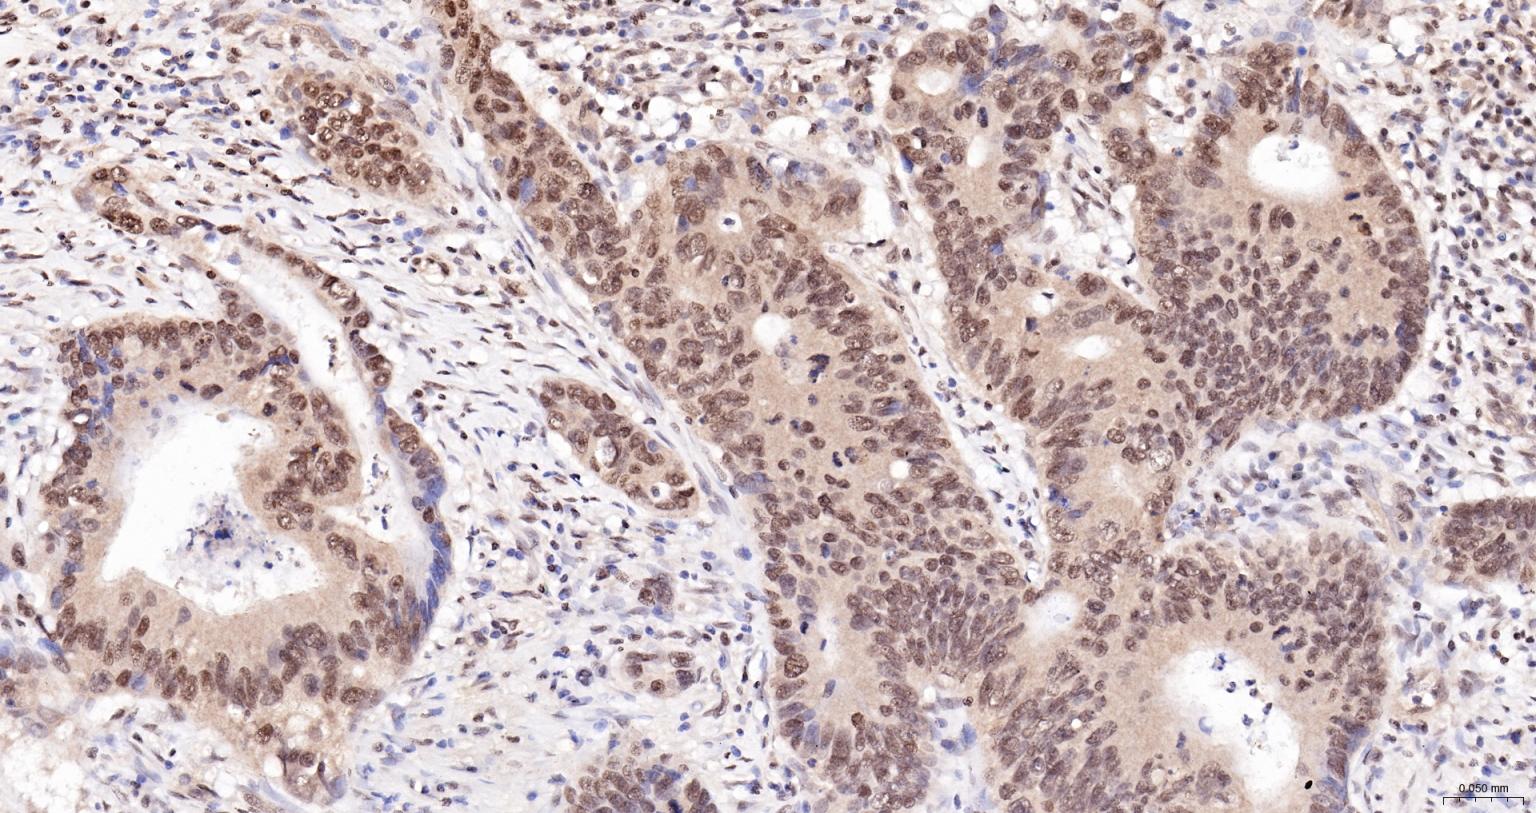

Paraformaldehyde-fixed, paraffin embedded Human Colon Cancer; Antigen retrieval by boiling in sodium citrate buffer (pH6.0) for 15 min; The section was incubated with CIDEC Polyclonal Antibody, Unconjugated (bs-6796R) at 1:200 overnight at 4°C, followed by conjugation to the bs-0295G-HRP and DAB (C-0010) staining.